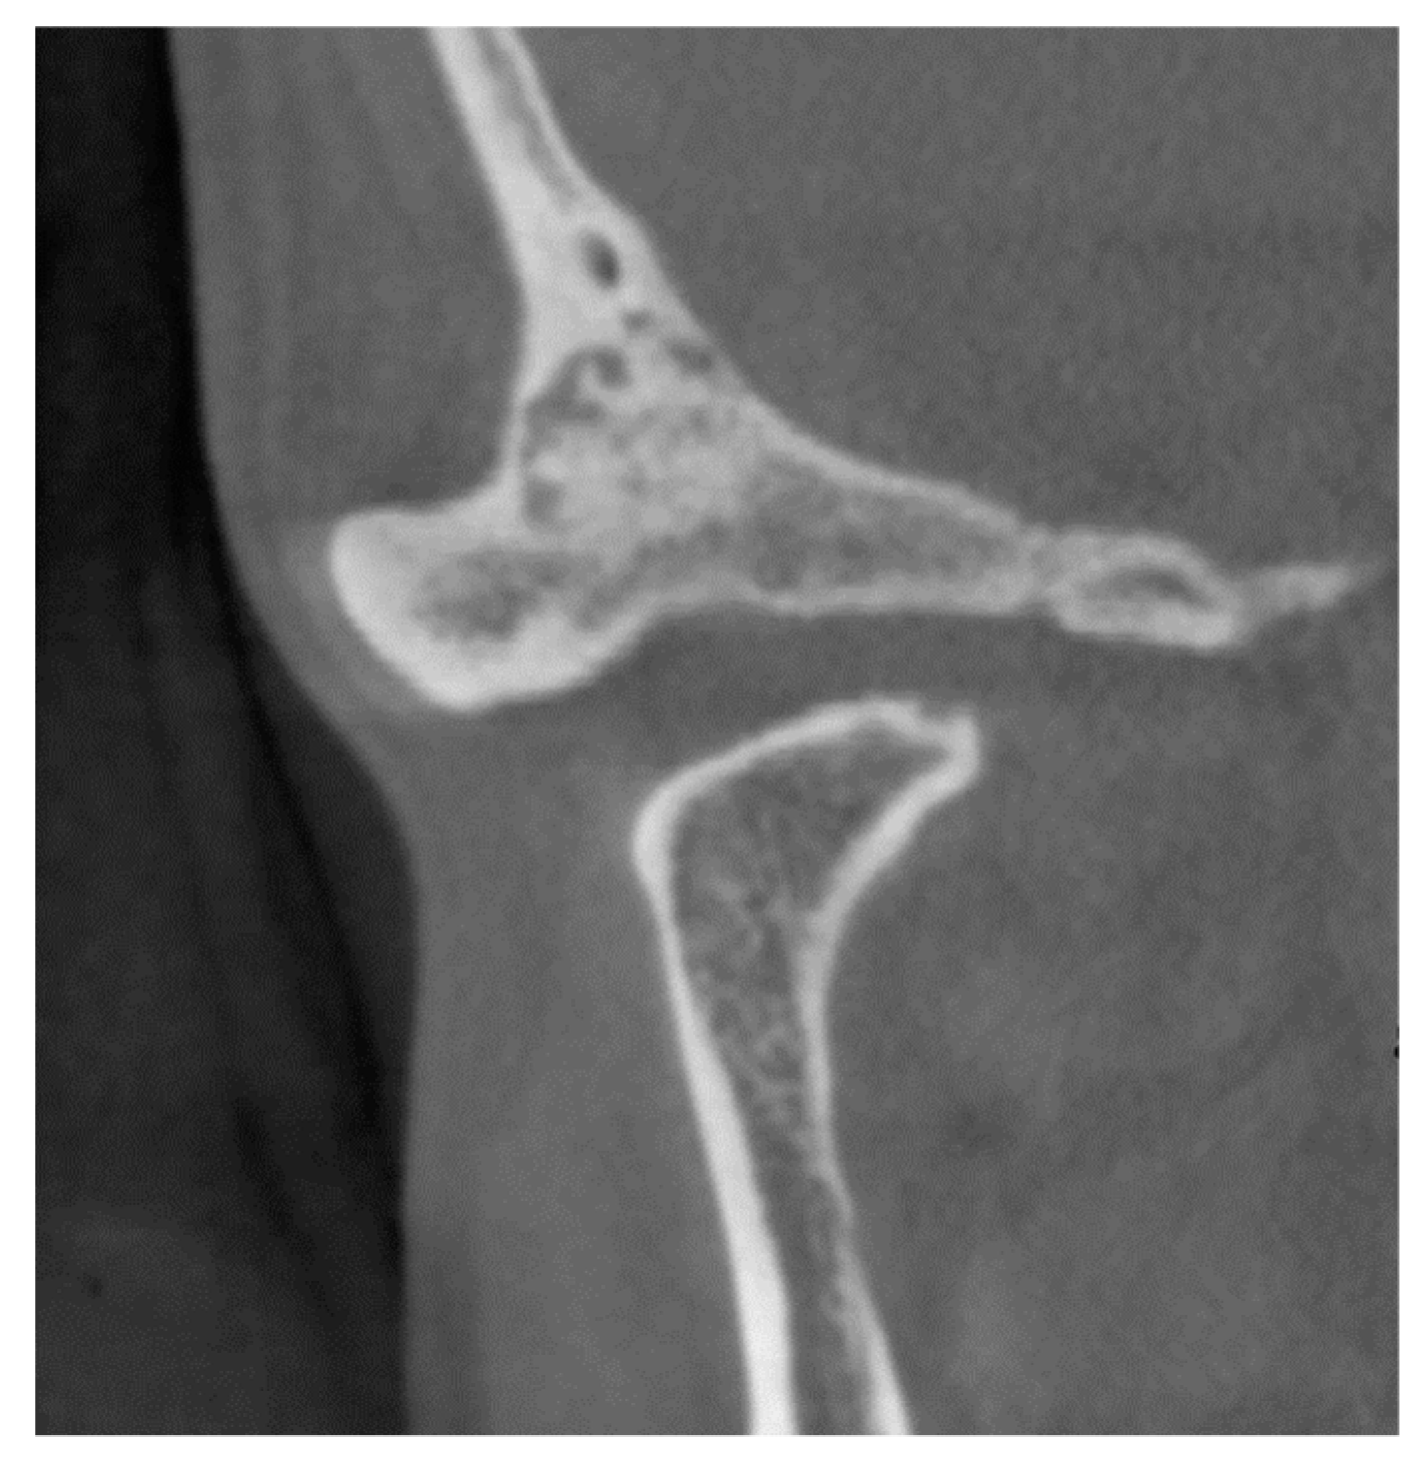

2.1. Patient 1